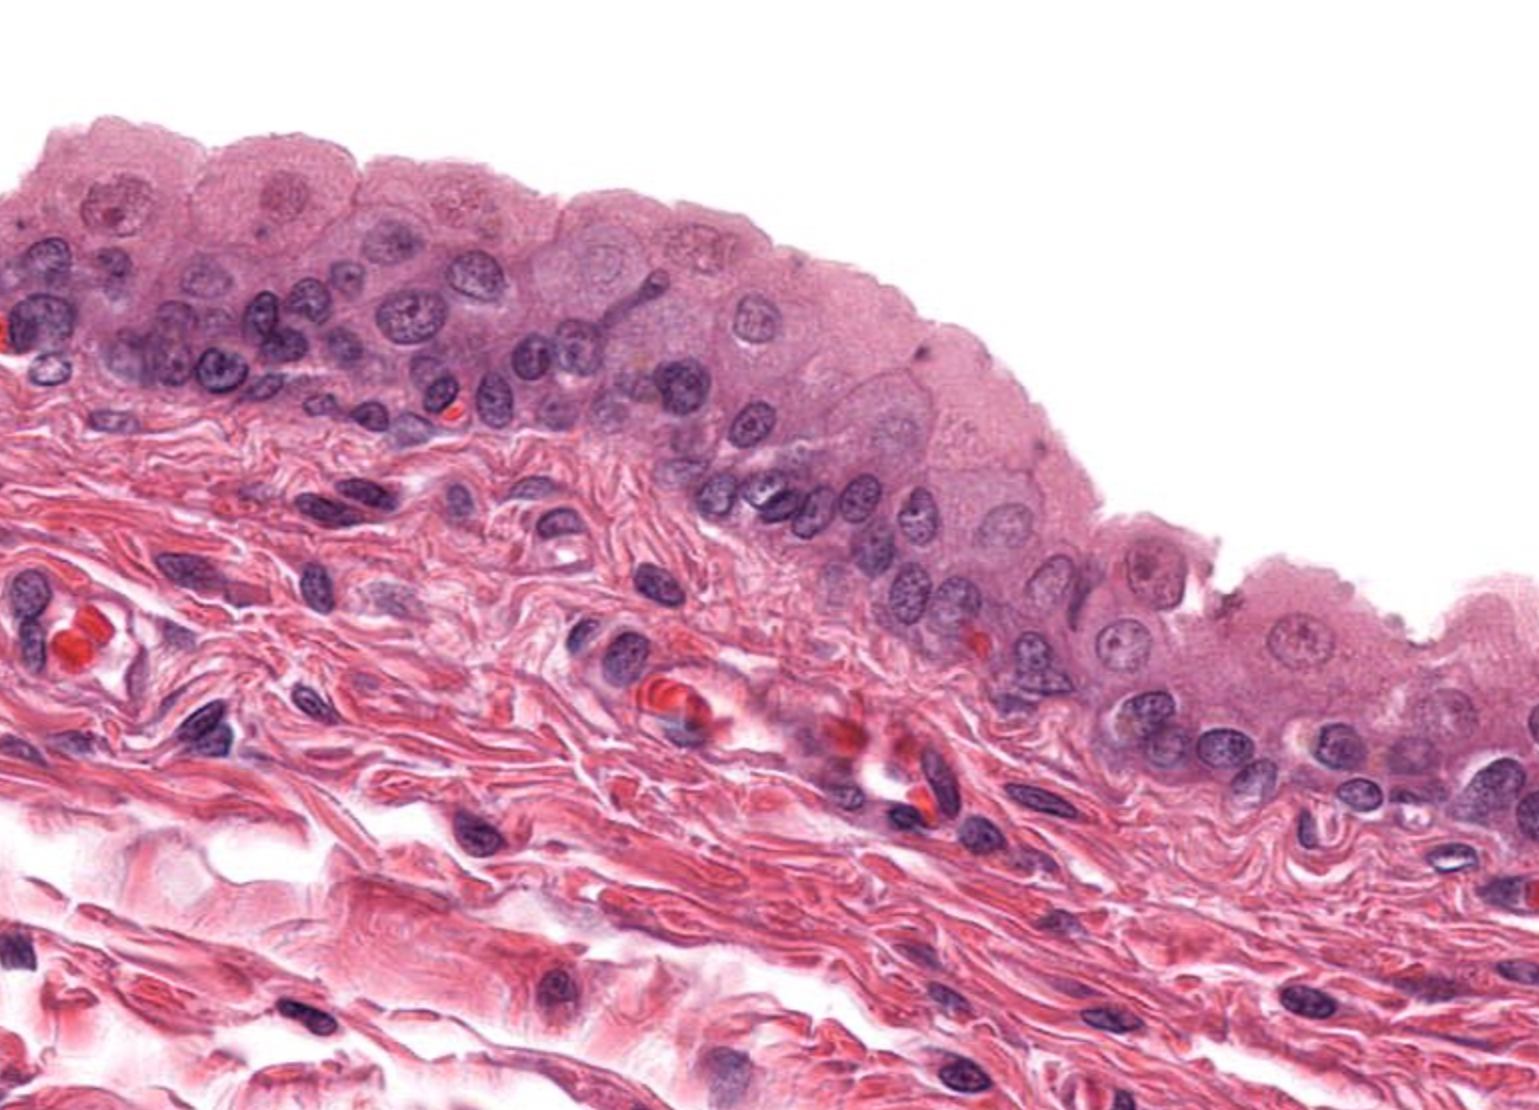

Tissue: nonkeratinized stratified squamous epithelium

Location: anterior surface of cornea

Function:

• protects underlying tissues in areas subject to ABRASION

• surface is exposed to air and is non-keratinized, the epithelium must be kept constantly moist with tears.